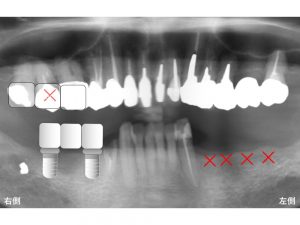

最終的には親知らず部分にはインプラント治療はせずに

2本のインプラントを埋め込み、

3歯分の被せ物を作成するインプラントブリッジとしました。

以下が治療後です。

今後は下顎左側の奥歯の欠損部の治療となります。